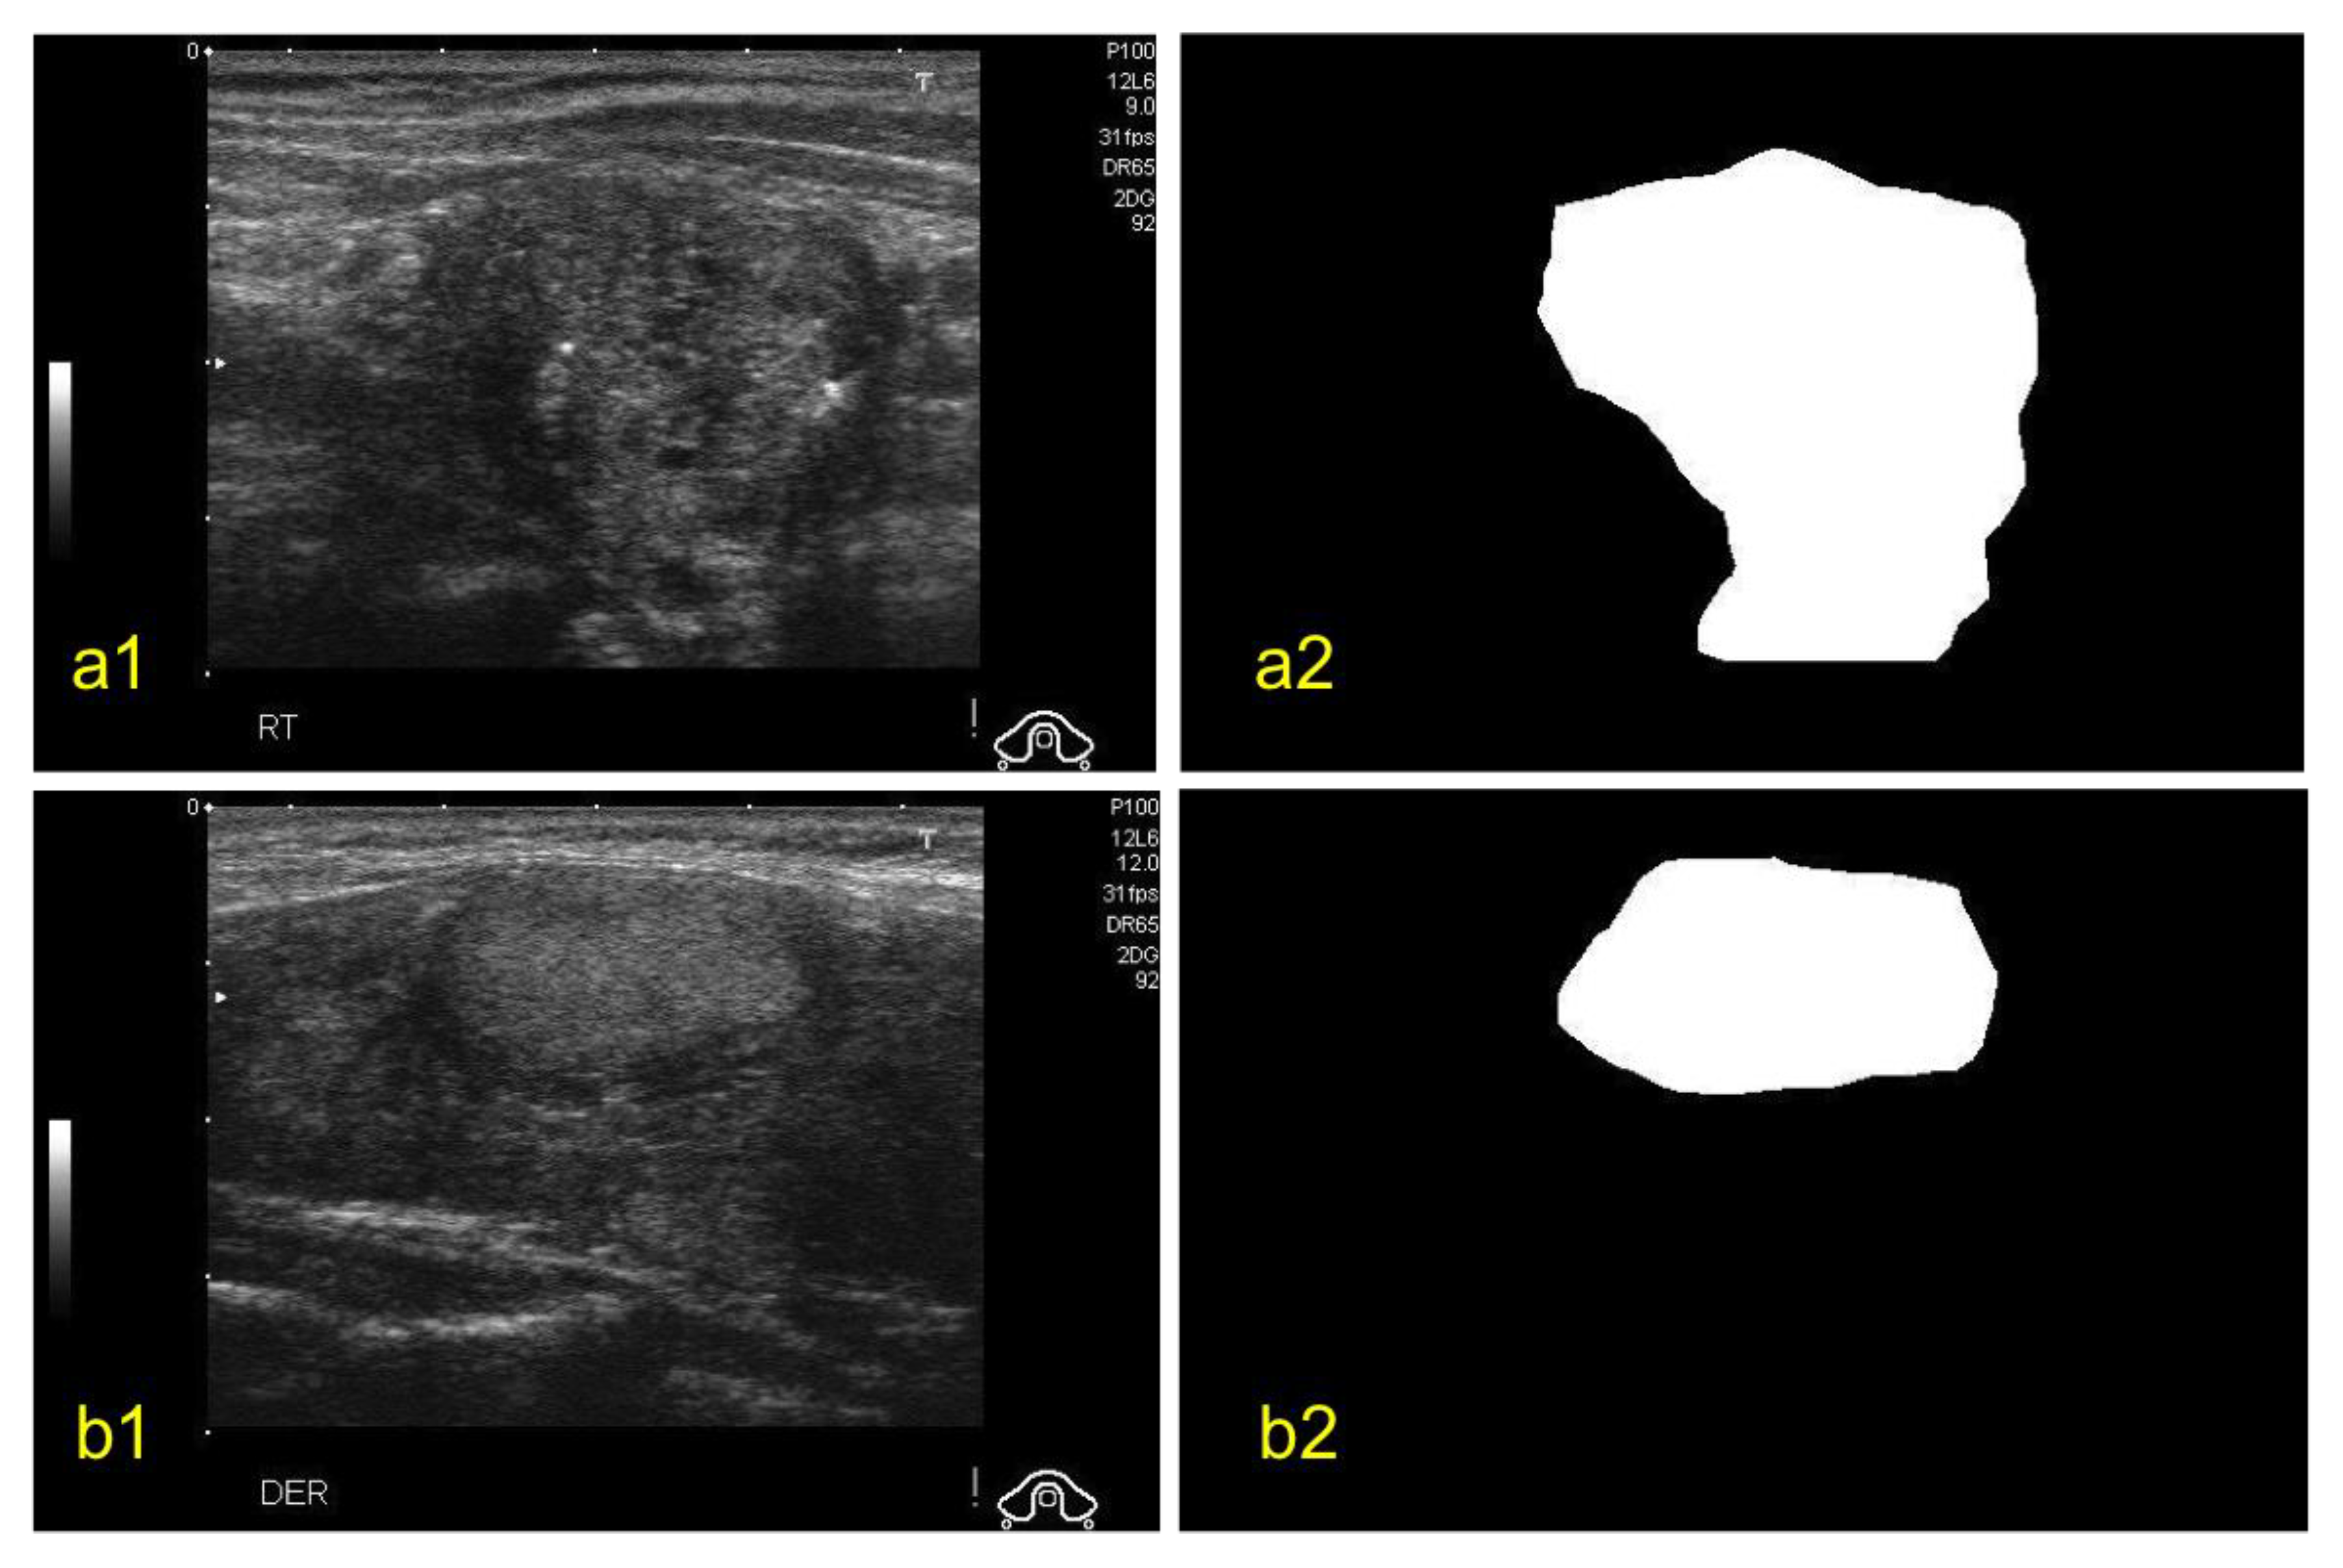

For this study, we used the Digital Database of Thyroid Ultrasound Images (DDTI) open-access dataset of thyroid nodule ultrasound images from the Instituto de Diagnostico Medico (IDIME) [19]. The dataset consists of a total of 99 cases with 2D ultrasound images from different patients that are annotated and classified based on TIRADS classification. The dataset is divided into JPEG files and XML files. Each image has a resolution of 560 × 315. Each image has a corresponding XML file. The XML files provided a detailed classification for each of the nodules. The ground truth (GT) for each of the nodules was generated by experienced physicians and is available in the form of coordinates in the XML file. An example of benign and malignant nodules along with their GTs can be seen in Figure 2. In this study, we only considered two labels (benign and malignant) rather than all the TIRADS labels.

Figure 2.

Examples of ultrasound images of thyroid nodules (a1) malignant nodule, (a2) its ground truth, (b1) benign nodule and (b2) its ground truth [19].